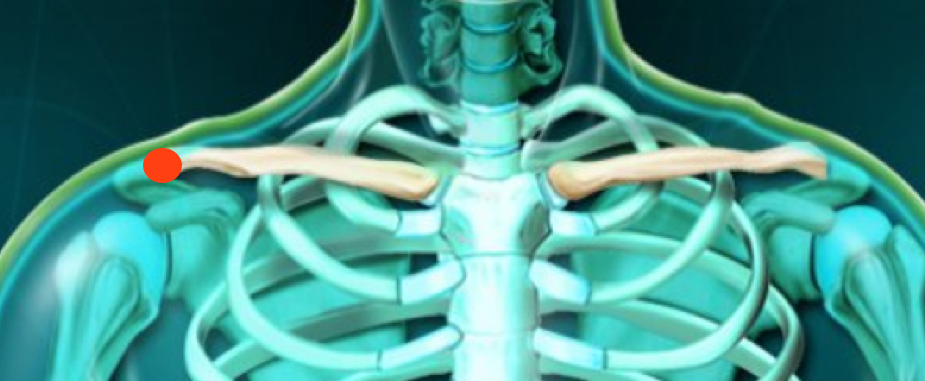

AC douleur locale

Le patient montre souvent la zone de lésion avec l’index de sa main opposée (pointing test)